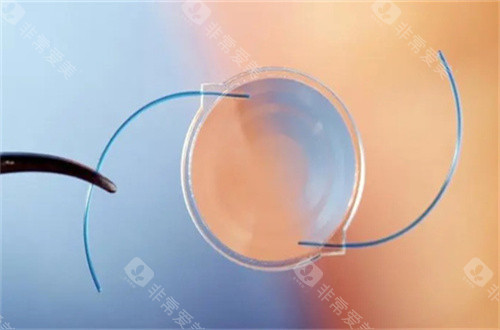

医院采用的手术方式主要有超声乳化白内障吸除术联合人工晶状体植入术等,这些手术方式具有切口小、改善快等优点。

不同的白内障手术方式和人工晶状体等材料的价格差异较大,这会直接影响报销金额。

一些高端的手术方式和进口的人工晶状体价格较高,虽然部分费用可以报销,但报销后患者仍需承担较大的自费部分。

而选择一些性价比高的国产材料和常规手术方式,报销后患者的自费金额相对会少一些。